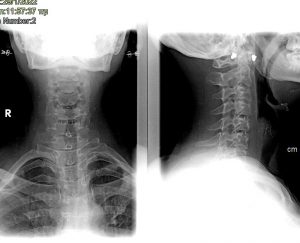

Διενεργήθηκε πρόσθια δισκεκτομή και αποσυμπίεση των ριζών στα επίπεδα Α4/5 & Α5/6

Η ασθενής παρουσίασε άμεση και πλήρη βελτίωση των συμπτωμάτων της.